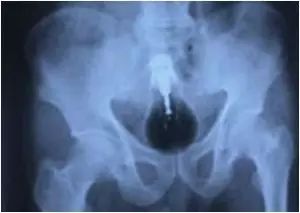

10.巴基斯坦一名囚犯的透视,发现有个灯泡停留在他的大肠。得知结果的他十分惊讶并且和家人分享了这张X光片。

巴基斯坦一名囚犯的透视,发现有个灯泡停留在他的大肠